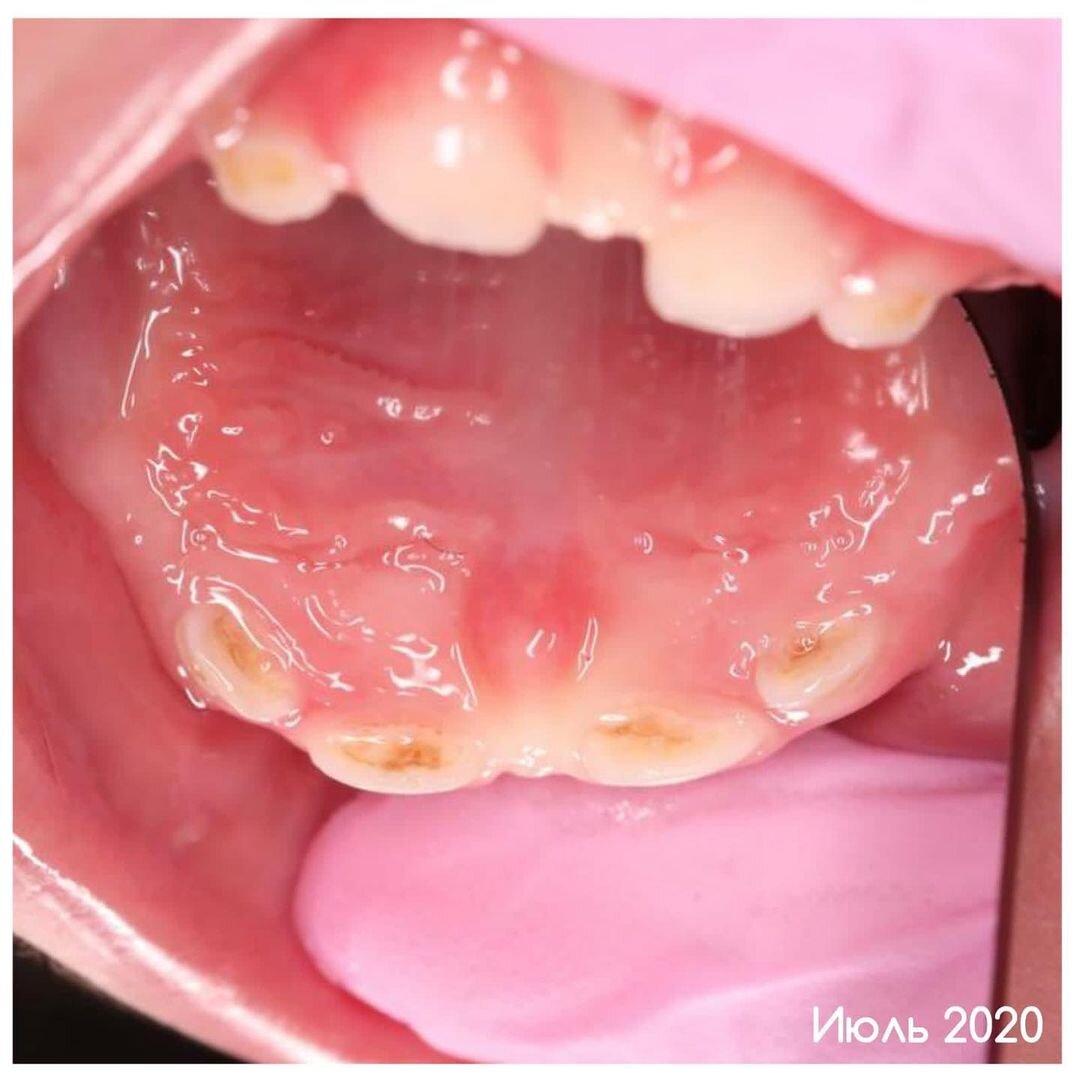

На момент обращения в июле 2020 года маленькому пациенту был всего 1 год. И уже все верхние центральные зубы были поражены кариесом. Просмотрите фото. Там поймёте. По объективным для родителей причинам они решили лечение не проводить. Очень хотелось подождать, пока ребёнок подрастёт и пойдёт на контакт. Плюс далеко не все реально оценивают «возможности» кариеса. В раннем детском возрасте он настолько агрессивен, что буквально сжирает зубы ребёнка. Примеров приводила массу. В октябре 2021-го пациенты пришли снова. Усугубившаяся картина перед вами на фото. Не забудьте просмотреть все фотки. Там наглядно. Кариес на резцах уже перерос в пульпит. А это уже совсем другой диагноз. Совсем другая тактика лечения — гораздо сложнее. Соответственно, вырастает и стоимость. Стоит ли говорить, что ребёнок так и не достиг возраста сотрудничества со стоматологом? К сожалению, нет. Лечение проводилось в условиях медикаментозного сна. Малыша приняла в свои заботливые руки детский стоматолог Ольга Нови

На момент обращения в июле 2020 года маленькому пациенту был всего 1 год.

И уже все верхние центральные зубы были поражены кариесом.